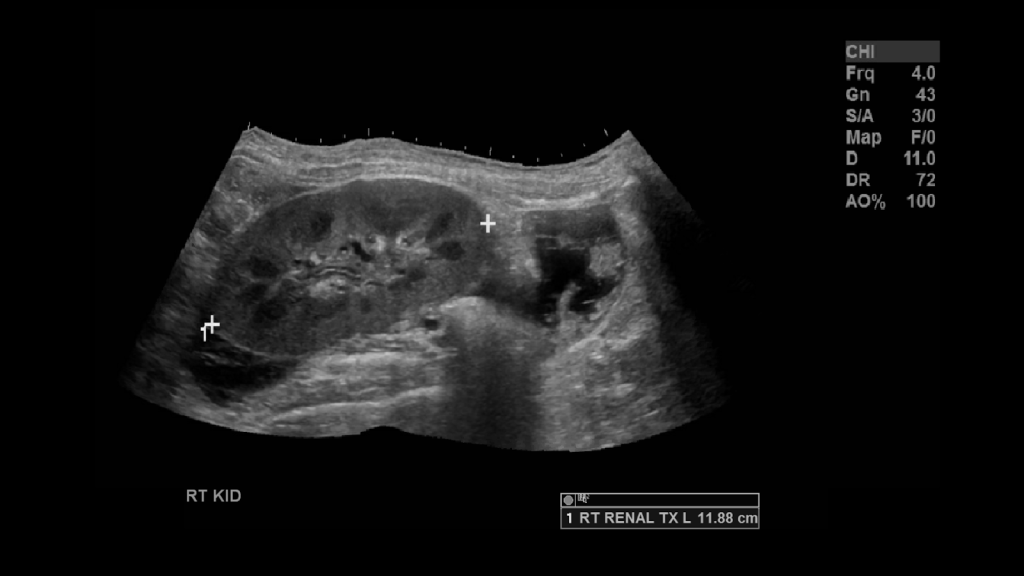

I like to begin the exam examining the native kidneys. Now a transplant recipient is likely to have suffered some chronic kidney disease, as such the native kidneys may be scarred, atrophic and in some cases imperceptible due to sever atrophy or surgery. In either case image the right and left renal fossa.

In full sized adults you’ll observe the kidney in the right iliac fossa. Image the kidney in sagittal and transverse planes. Utilize Doppler to see the vascularity. Measure the kidney. If the kidney is too large you can take a panoramic image. Make sure to take not of the echogenicity, check for edema, areas of no vascularity, look for collections.